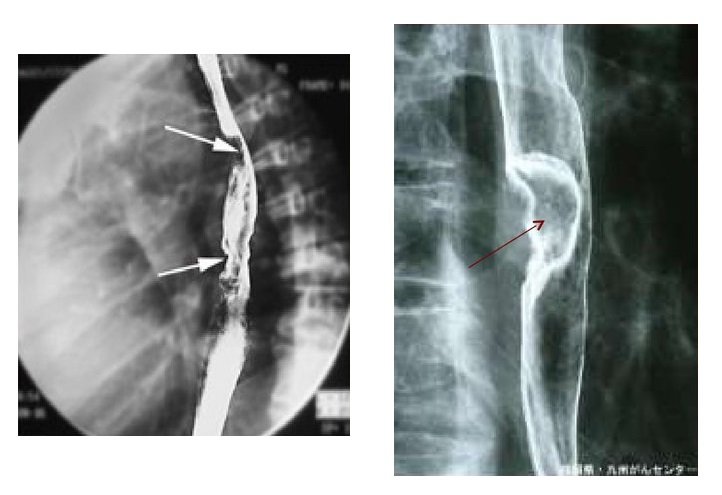

- рентгенография — обнаруживает присутствие очагов рака в средостении и лёгких. Контрастный рентген с барием позволяет определить новообразование на стенках пищевода;

- эзофагоскопия (эндоскопическое исследование) помогает тщательно обследовать внутренние стенки и слизистую, определяет, как выглядит опухоль, уточняет её форму, поверхность, размер, выявляет наличие осложнений, участков кровоточивости и некрозов. Во время эндоскопического ультразвукового исследования проверяют степень прорастания новообразования в стенки пищевода и прилегающие органы и ткани;